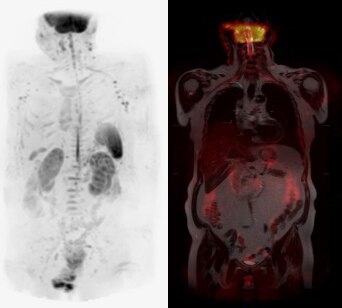

前機種のMRIは寝台が固定式でしたので、患者が汎用ストレッチャーで検査に来た場合、専用ストレッチャーに乗り換えた後MRI室へ入室し、その後さらにMRIの寝台へ移動を行っていました。現在は、脱着式の寝台であるeXpress Dockable Tableを使用することにより、患者を汎用ストレッチャーから直接MRIの寝台へ移動することが可能となりました。患者の移動に費やす作業が2回の行程から1回の行程になったことで、患者入れ替えに掛かる時間が短縮しました。また、MRI検査スタッフ以外の職員が患者移動のために撮影室に入室することが無くなったので所持品の吸着事故が発生していません。

今回、脱着式寝台を初めて使用しますが、脱着時の手順についてはガントリー上部のモニターに表示される手順ガイドを確認しながら操作しています。

図1 脱着式寝台

(赤丸:脱着操作時にガントリーモニタに表示される手順ガイド)